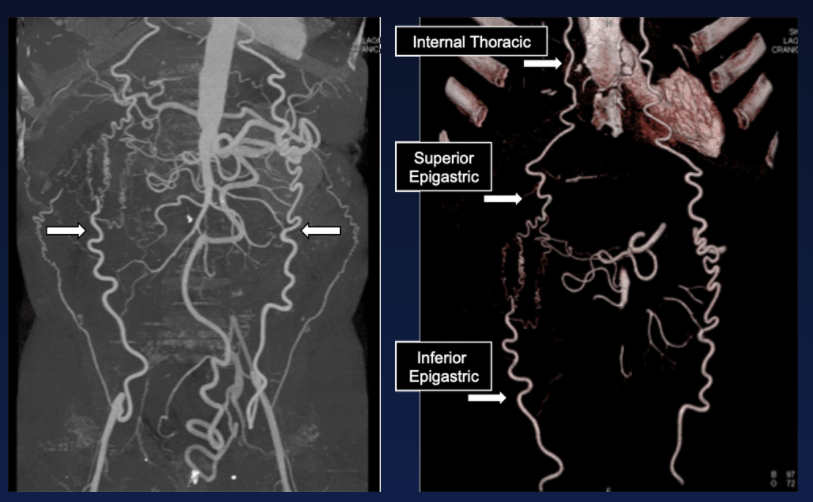

Collatérale de Winslow

- Voie de dérivation lors d’occlusion de l’artère iliaque externe

- Entre l’artère épigastrique supérieure et inférieure

- Subclavière → Mammaire interne → Epg-Sup → Epg-Inf → Iliaque Ext